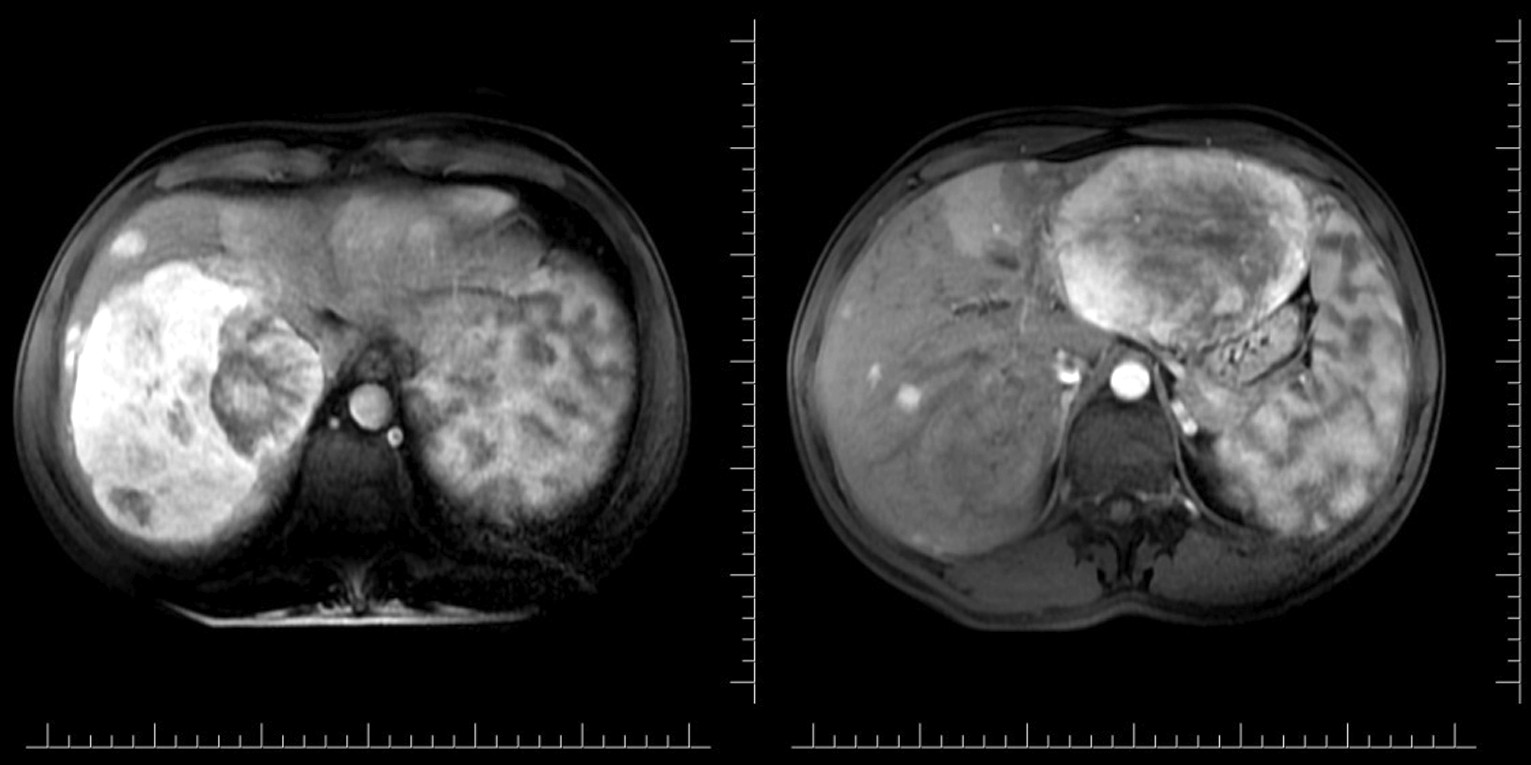

При МСКТ органов брюшной полости (рис. 1) в паренхиме печени определяются множественные разнокалиберные (от 2–3 мм в диаметре) округлые образования с неровными, четкими контурами, наиболее крупные имеют диаметр 13,2 см (правая доля) и 13 см (левая доля), их структура кистозно-солидная; в артериальную и венозную фазы контрастирования отмечается выраженное неравномерное накопление контрастного препарата, прослеживается развитая сосудистая сеть, других изменений органов брюшной полости и забрюшинного пространства не выявлено. Заключение: объемные гиперваскулярные образования в паренхиме печени.

Рис. 1. МСКТ брюшной полости: артериальная фаза (описание в тексте).